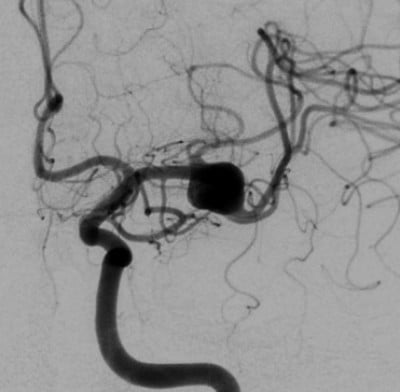

Dzięki temu uratowali życie 34-letniego mężczyzny, którego nikt już nie chciał operować. Potrzebne były dwie operacje, ale bez konieczności otwierania czaszki. Pierwsza została przeprowadzona w Wałbrzychu, kolejna już w Uniwersyteckim Szpitalu Klinicznym. Jak tłumaczy Marcin Miś przez cewnik wprowadzony przez tętnicę udową dotarli do mózgu gdzie wyłączyli niebezpieczny rejon:

Zabieg został przeprowadzony przez małe nacięcie w tętnicy udowej i wprowadzenie do mózgu cewnika. W plątaninie tętnic lekarze zrobili nowe obejście zagrożonego obszaru, wyłączając tętniaka. Pacjent czuje się dobrze i normalnie funkcjonuje.